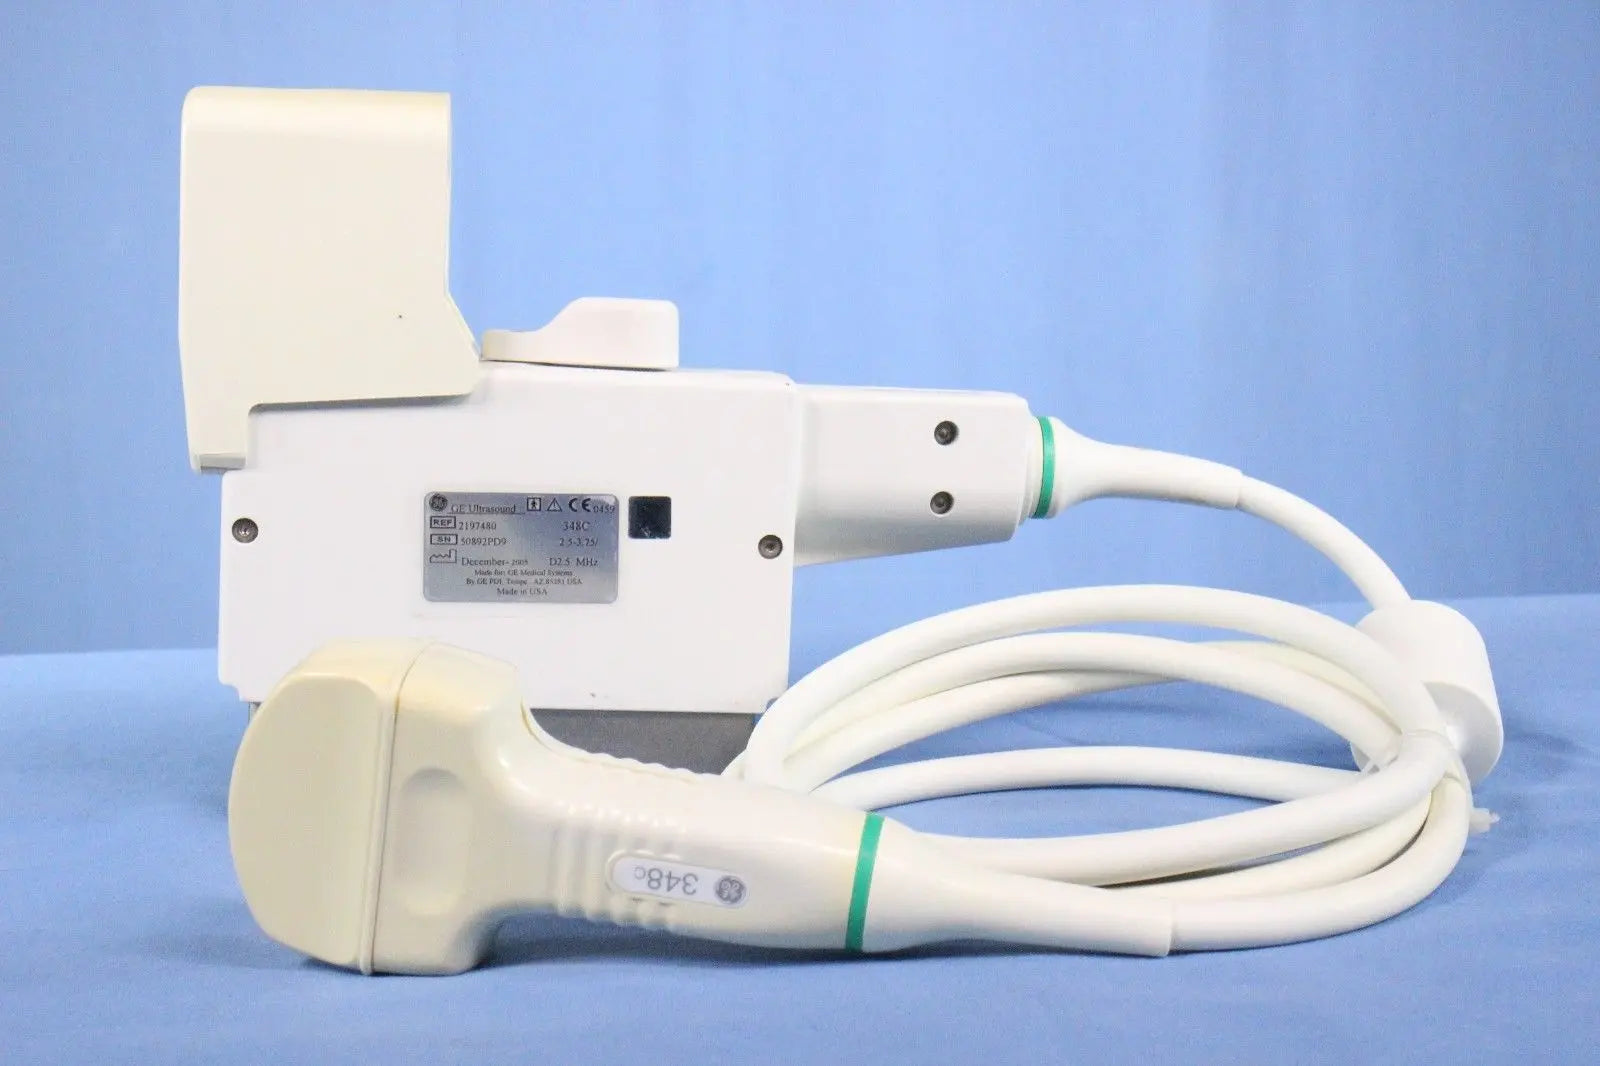

DIAGNOSTIC ULTRASOUND MACHINES FOR SALE

GE 348c Ultrasound convex ultrasound transducer

Sale price$ 1,439.90

DIAGNOSTIC ULTRASOUND MACHINES FOR SALE

GE 348C 2197480 ULTRASOUND TRANSDUCER PROBE

Sale price$ 3,599.78